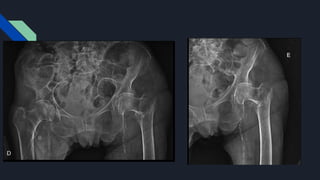

PACIENTE NA MESA DE TRAÇÃO ORTOPÉDICA, E DECUBITO DORSAL HORIZONTAL SOB

RAQUIANESTESIA; - REDUÇÃO INCRUENTA, NA MESA DE TRAÇÃO, SOB VIZUALIZAÇÃO POR

FLUOROSCOPIA;

- ASSEPSIA + ANTISEPSIA + COLOCAÇÃO DE CAMPOS ESTÉREIS EM MIE;

- INCISÃO LATERAL, NA ALTURA DO TROCANTER MAIOR + DIVULSÃO + HEMOSTASIA;

- ACESSO AO TROCANTER MAIOR + PASSAGEM DE SOVELA + PASSAGEM DE FIO GUIA;

- CHECADO EM FLUOROSCOPIA;

- FRESA MANUAL INICIAL + FRESAGEM PROGRESSIVA;

- PASSAGEM DE TUTOR INTRAMEDULAR CURTO Nº11X200, CHECADO EM FLUOROSCOPIA;

- RETIRADO FIO GUIA + MARCAÇÃO DO BLOQUEIO CEFÁLICO + INCISÃO + DIVULSÃO;

- PASSAGEM DE FIO GUIA CEFÁLICO, CHECADO EM FLUOROSCOPIA;

- FRESA INICIAL COM STOP + FRESAGEM CEFÁLICA;

- PASSAGEM DE PARAFUSO CEFÁLICO , CHECADO EM FLUOROSCOPIA;

- MARCAÇÃO DO BLOQUEIO DISTAL GUIADO POR FLUOROSCOPIA;

- INCISÃO + PERFURAÇÃO + PASSAGEM DE PARAFUSO DE BLOQUEIO DISTAL;

- LAVAGEM COM SF0,9% + REVISÃO HEMOSTÁTICA + SUTURA + CURATIVO ESTÉRIL;

- RX CONTROLE;

- ENCAMINHO AO RPA SEM INTERCORRÊNCIAS.

• 12.

PACIENTE NA MESADE TRAÇÃO ORTOPÉDICA, E DECUBITO DORSAL HORIZONTAL SOB RAQUIANESTESIA; - REDUÇÃO INCRUENTA, NA MESA DE TRAÇÃO, SOB VIZUALIZAÇÃO POR FLUOROSCOPIA; - ASSEPSIA + ANTISEPSIA + COLOCAÇÃO DE CAMPOS ESTÉREIS EM MIE; - INCISÃO LATERAL, NA ALTURA DO TROCANTER MAIOR + DIVULSÃO + HEMOSTASIA; - ACESSO AO TROCANTER MAIOR + PASSAGEM DE SOVELA + PASSAGEM DE FIO GUIA; - CHECADO EM FLUOROSCOPIA; - FRESA MANUAL INICIAL + FRESAGEM PROGRESSIVA; - PASSAGEM DE TUTOR INTRAMEDULAR CURTO Nº11X200, CHECADO EM FLUOROSCOPIA; - RETIRADO FIO GUIA + MARCAÇÃO DO BLOQUEIO CEFÁLICO + INCISÃO + DIVULSÃO; - PASSAGEM DE FIO GUIA CEFÁLICO, CHECADO EM FLUOROSCOPIA; - FRESA INICIAL COM STOP + FRESAGEM CEFÁLICA; - PASSAGEM DE PARAFUSO CEFÁLICO , CHECADO EM FLUOROSCOPIA; - MARCAÇÃO DO BLOQUEIO DISTAL GUIADO POR FLUOROSCOPIA; - INCISÃO + PERFURAÇÃO + PASSAGEM DE PARAFUSO DE BLOQUEIO DISTAL; - CHECADO EM FLUOROSCOPIA; - LAVAGEM COM SF0,9% + REVISÃO HEMOSTÁTICA + SUTURA + CURATIVO ESTÉRIL; - RX CONTROLE; - ENCAMINHO AO RPA SEM INTERCORRÊNCIAS.